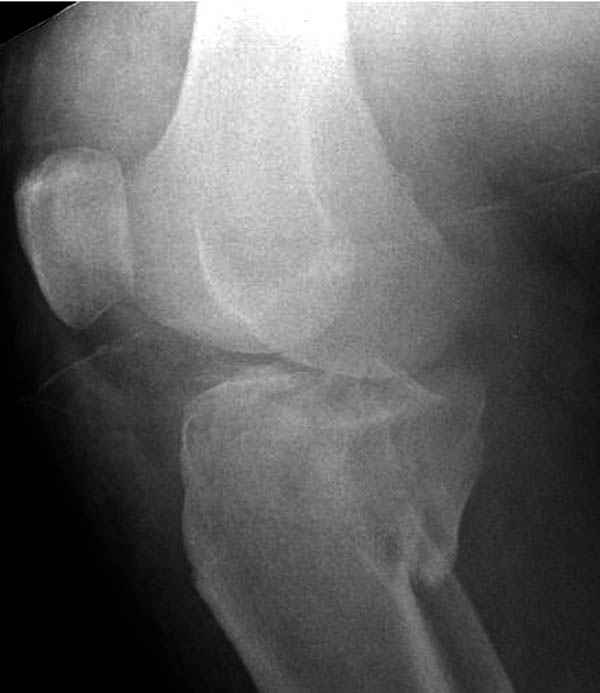

Трудно поверить, что разрекламированная Ортопедическая школа Восточной Украины позволяет такие странные снимки? На прямом снимке сохранен общий контур плато, но не известна судьба импрессии суставной поверхности. На полубоковой?, оставлен без репозиции задне-медиальный отдел, и навряд ли после такой фиксации можно удовлетвориться результатом.

Такая ситуация характерна для многих, когда принимается ошибочное решение, т.е пытаются фиксировать одним имплантом переломы двух мыщелков. Латеральная пластина приемлема только для тех случаев, когда сохраняется интактным медиальный диафизарный кортекс и отсутствует фрагментация на верхушке медиального перелома.

Здесь как раз тот случай, когда результат зависит не только от мастерства хирурга, но и от наличия современных методов исследования. Например, КТ которая поможет рассчитать направления шурупов и установку импланта. Кроме этого, поможет определиться с доступом.

На представленных предоперационных срезах КТ огромный задне-медиальный фрагмент расположен больше кзади, чем медиально. Для планирования, кроме поперечных срезов, надо ориентироваться на корональные срезы, которые укажут топографию верхушки медиального фрагмента.

Представленные снимки не информативны, нужны отдельные качественные снимки коленного сустава и голени без ротации.